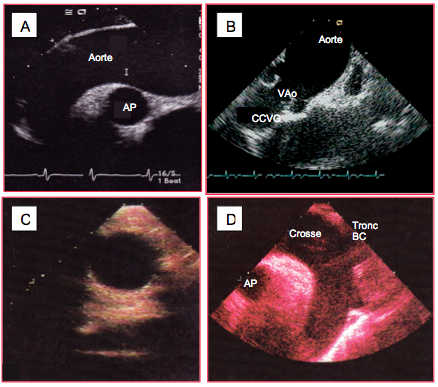

Figure 27.100 : Anévrysme du sinus de Valsalva droit en diastole (A) et en systole (B) (flèche jaune). La lésion est ici accompagnée d'un prolapsus de la cuspide aortique droite. C et D: anévrysme de la partie membraneuse du septum interventriculaire (flèche verte) en vue long-axe de l’aorte ascendante (C) et court-axe de la valve aortique (D). La confusion est aisée entre les deux pathologies.

L'anévrysme du sinus de Valsalva droit protrude dans la chambre de chasse droite, celui du sinus gauche dans la CCVG ou l'OG et celui du sinus non-coronaire dans la CCVD ou l'OD. La lésion devient symptomatique en cas de fistulisation dans une chambre de chasse ou une oreillette (voir Jonction ventriculo-artérielle).